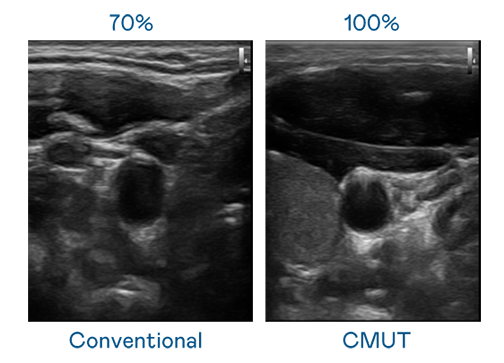

CMUT 技術是一種用電容式微機電元件來產生超音波訊號的技術。與傳統 PZT 壓電式技術相比,CMUT 頻寬增加 30%,更寬頻的超音波訊號讓影像解析度大幅提升,是實現高影像品質醫療超音波掃描、促進精準醫療發展的關鍵技術。

超音波影像的解析度高低,首先取決於探頭能發出的訊號頻寬。尊龙时凯人生就是搏官网 CMUT 可提供高清晰的超音波訊號,提供高頻寬、高靈敏度、影像紋理細節更高的超音波影像,協助醫護人員縮短影像判讀時間及利用精準的醫療影像進行診斷。